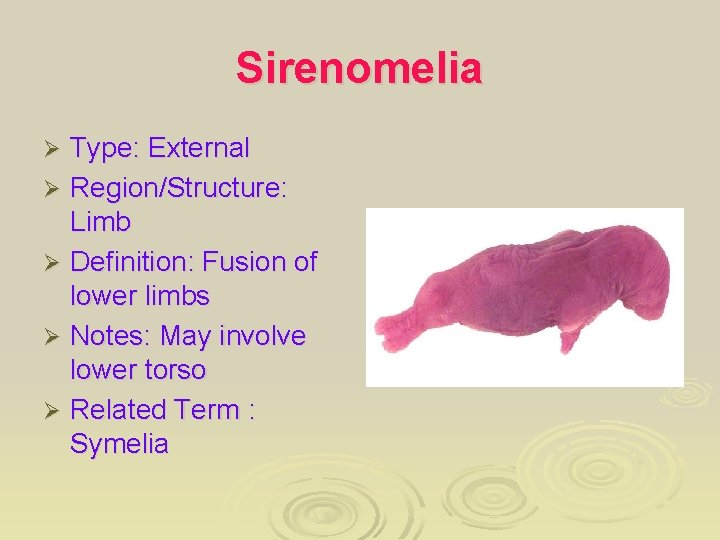

Sirenomelia Type: External Ø Region/Structure: Limb Ø Definition: Fusion of lower limbs Ø Notes: May involve lower torso Ø Related Term : Symelia Ø